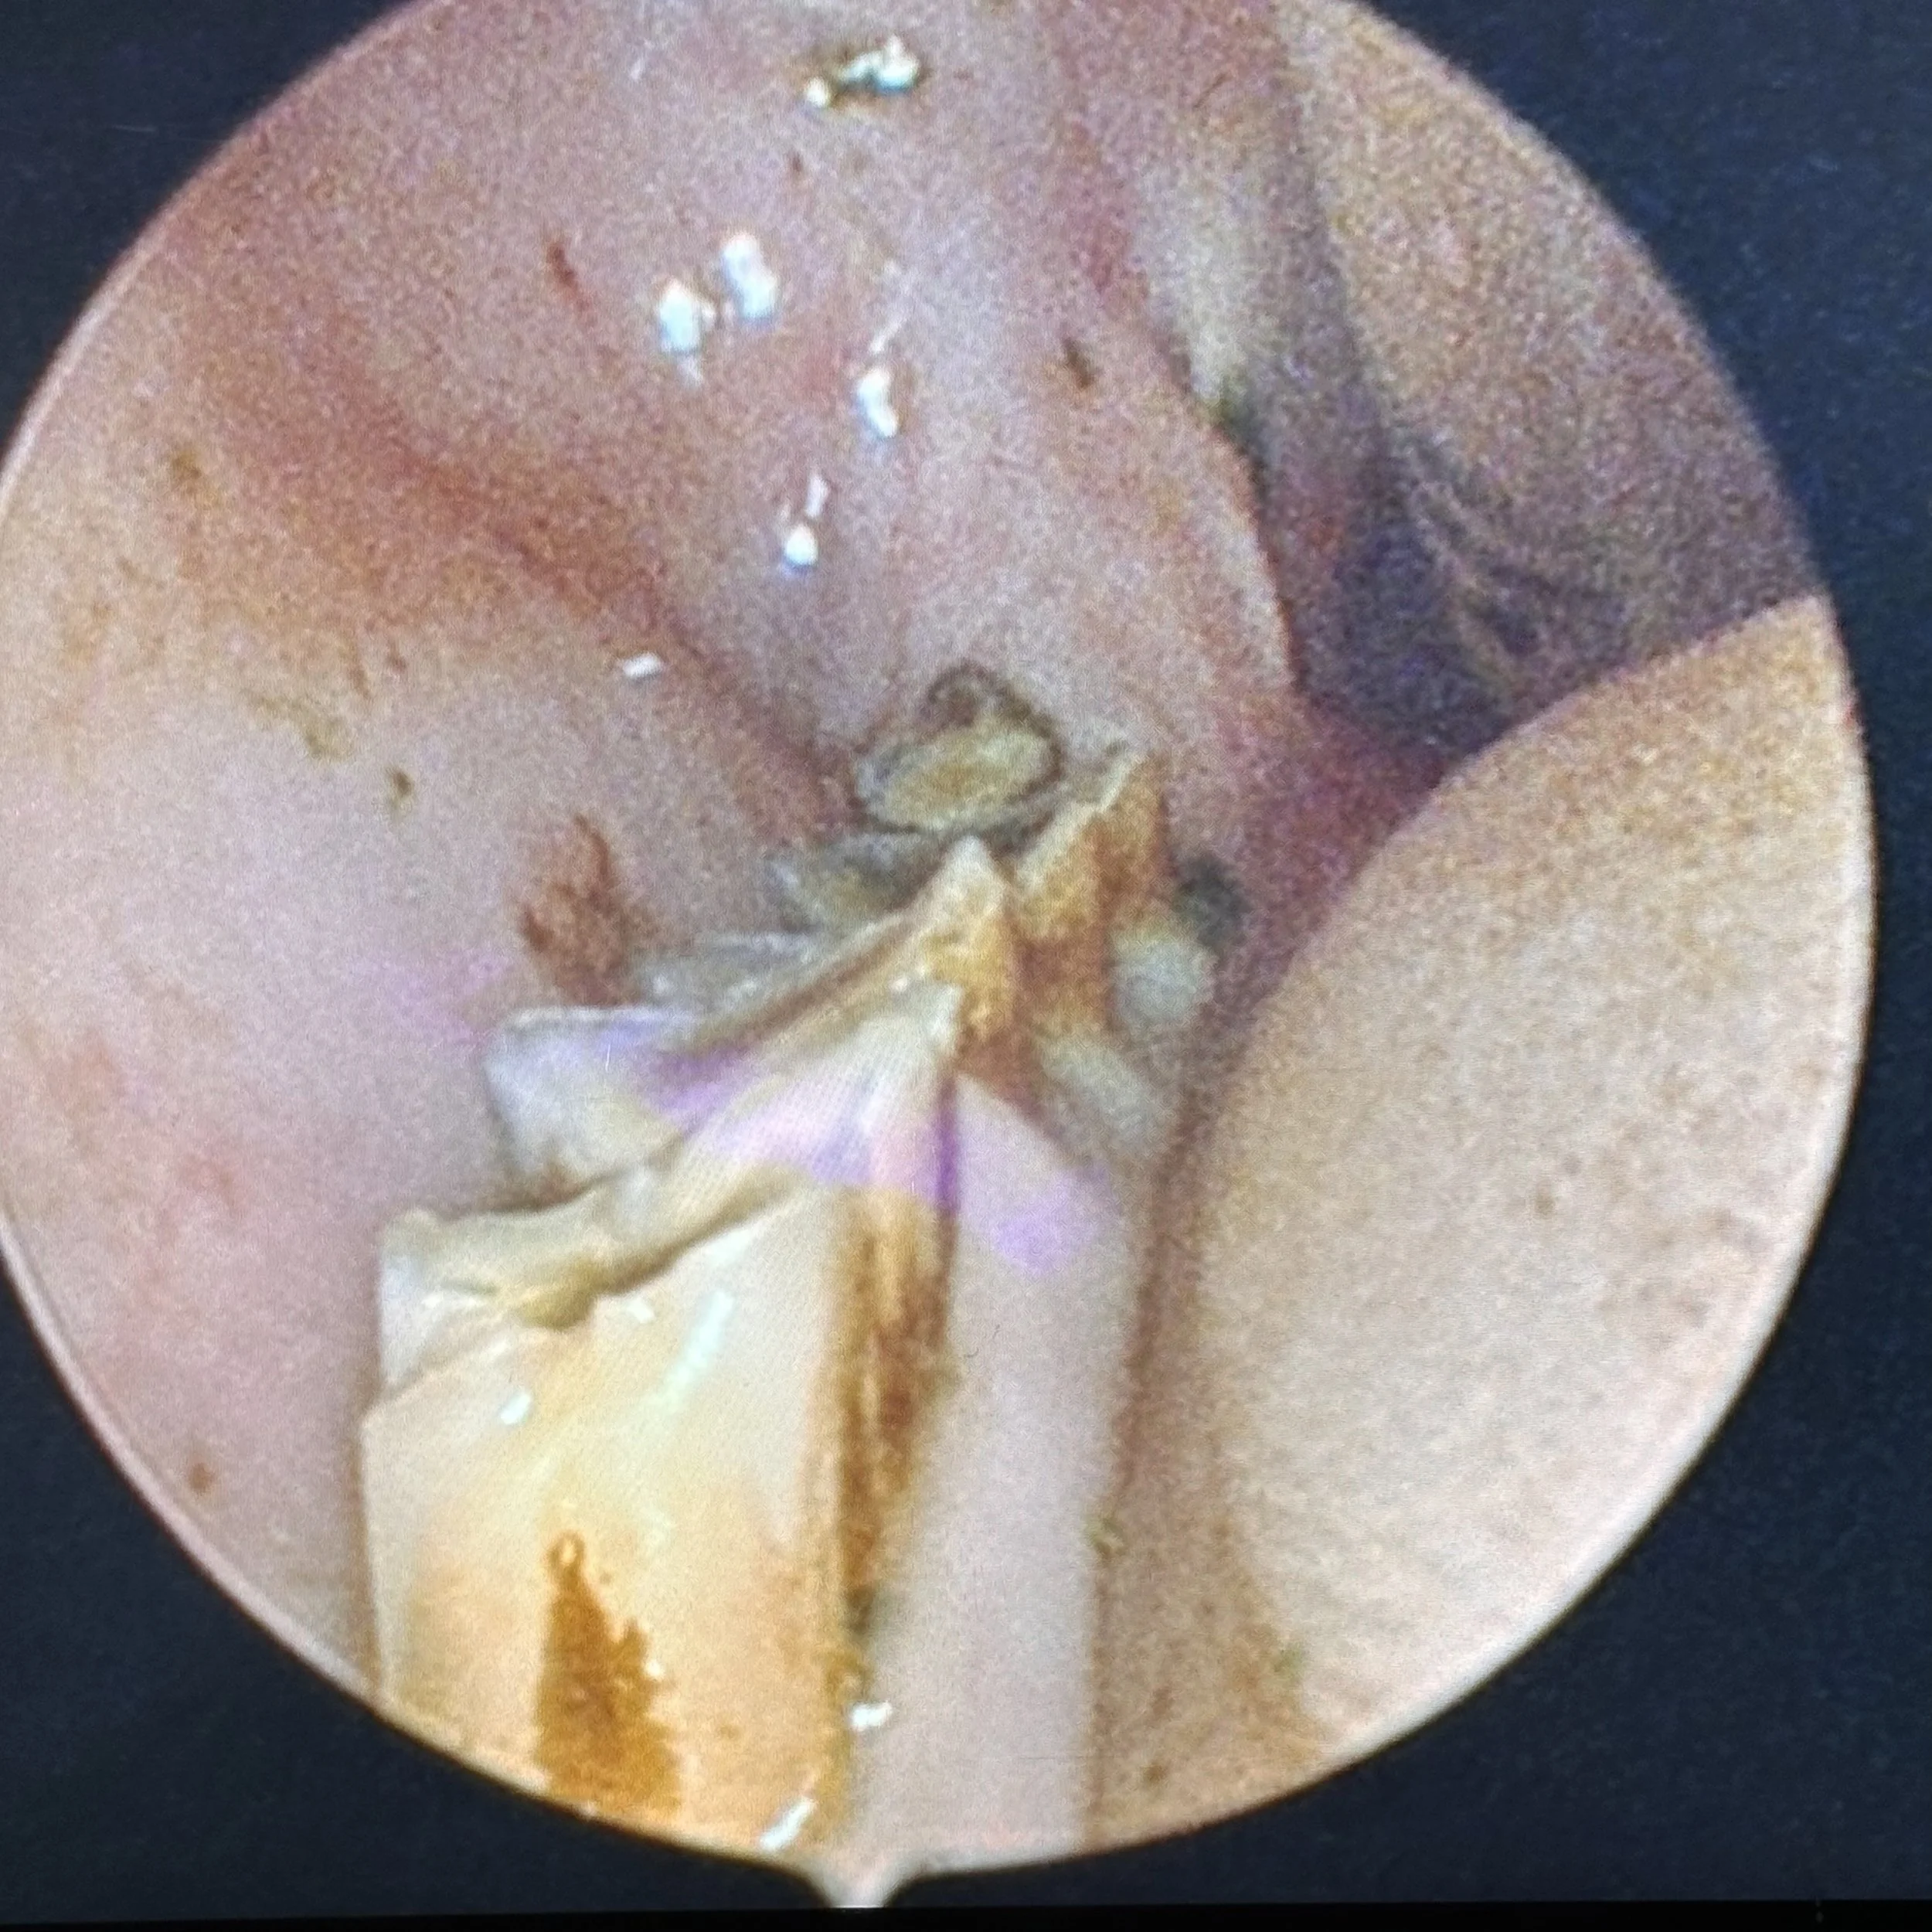

Rabbit Dentistry

Dental disease is one of the most common reasons pet rabbits present to veterinary clinics. It can produce a wide variety of clinical signs and varies in severity.